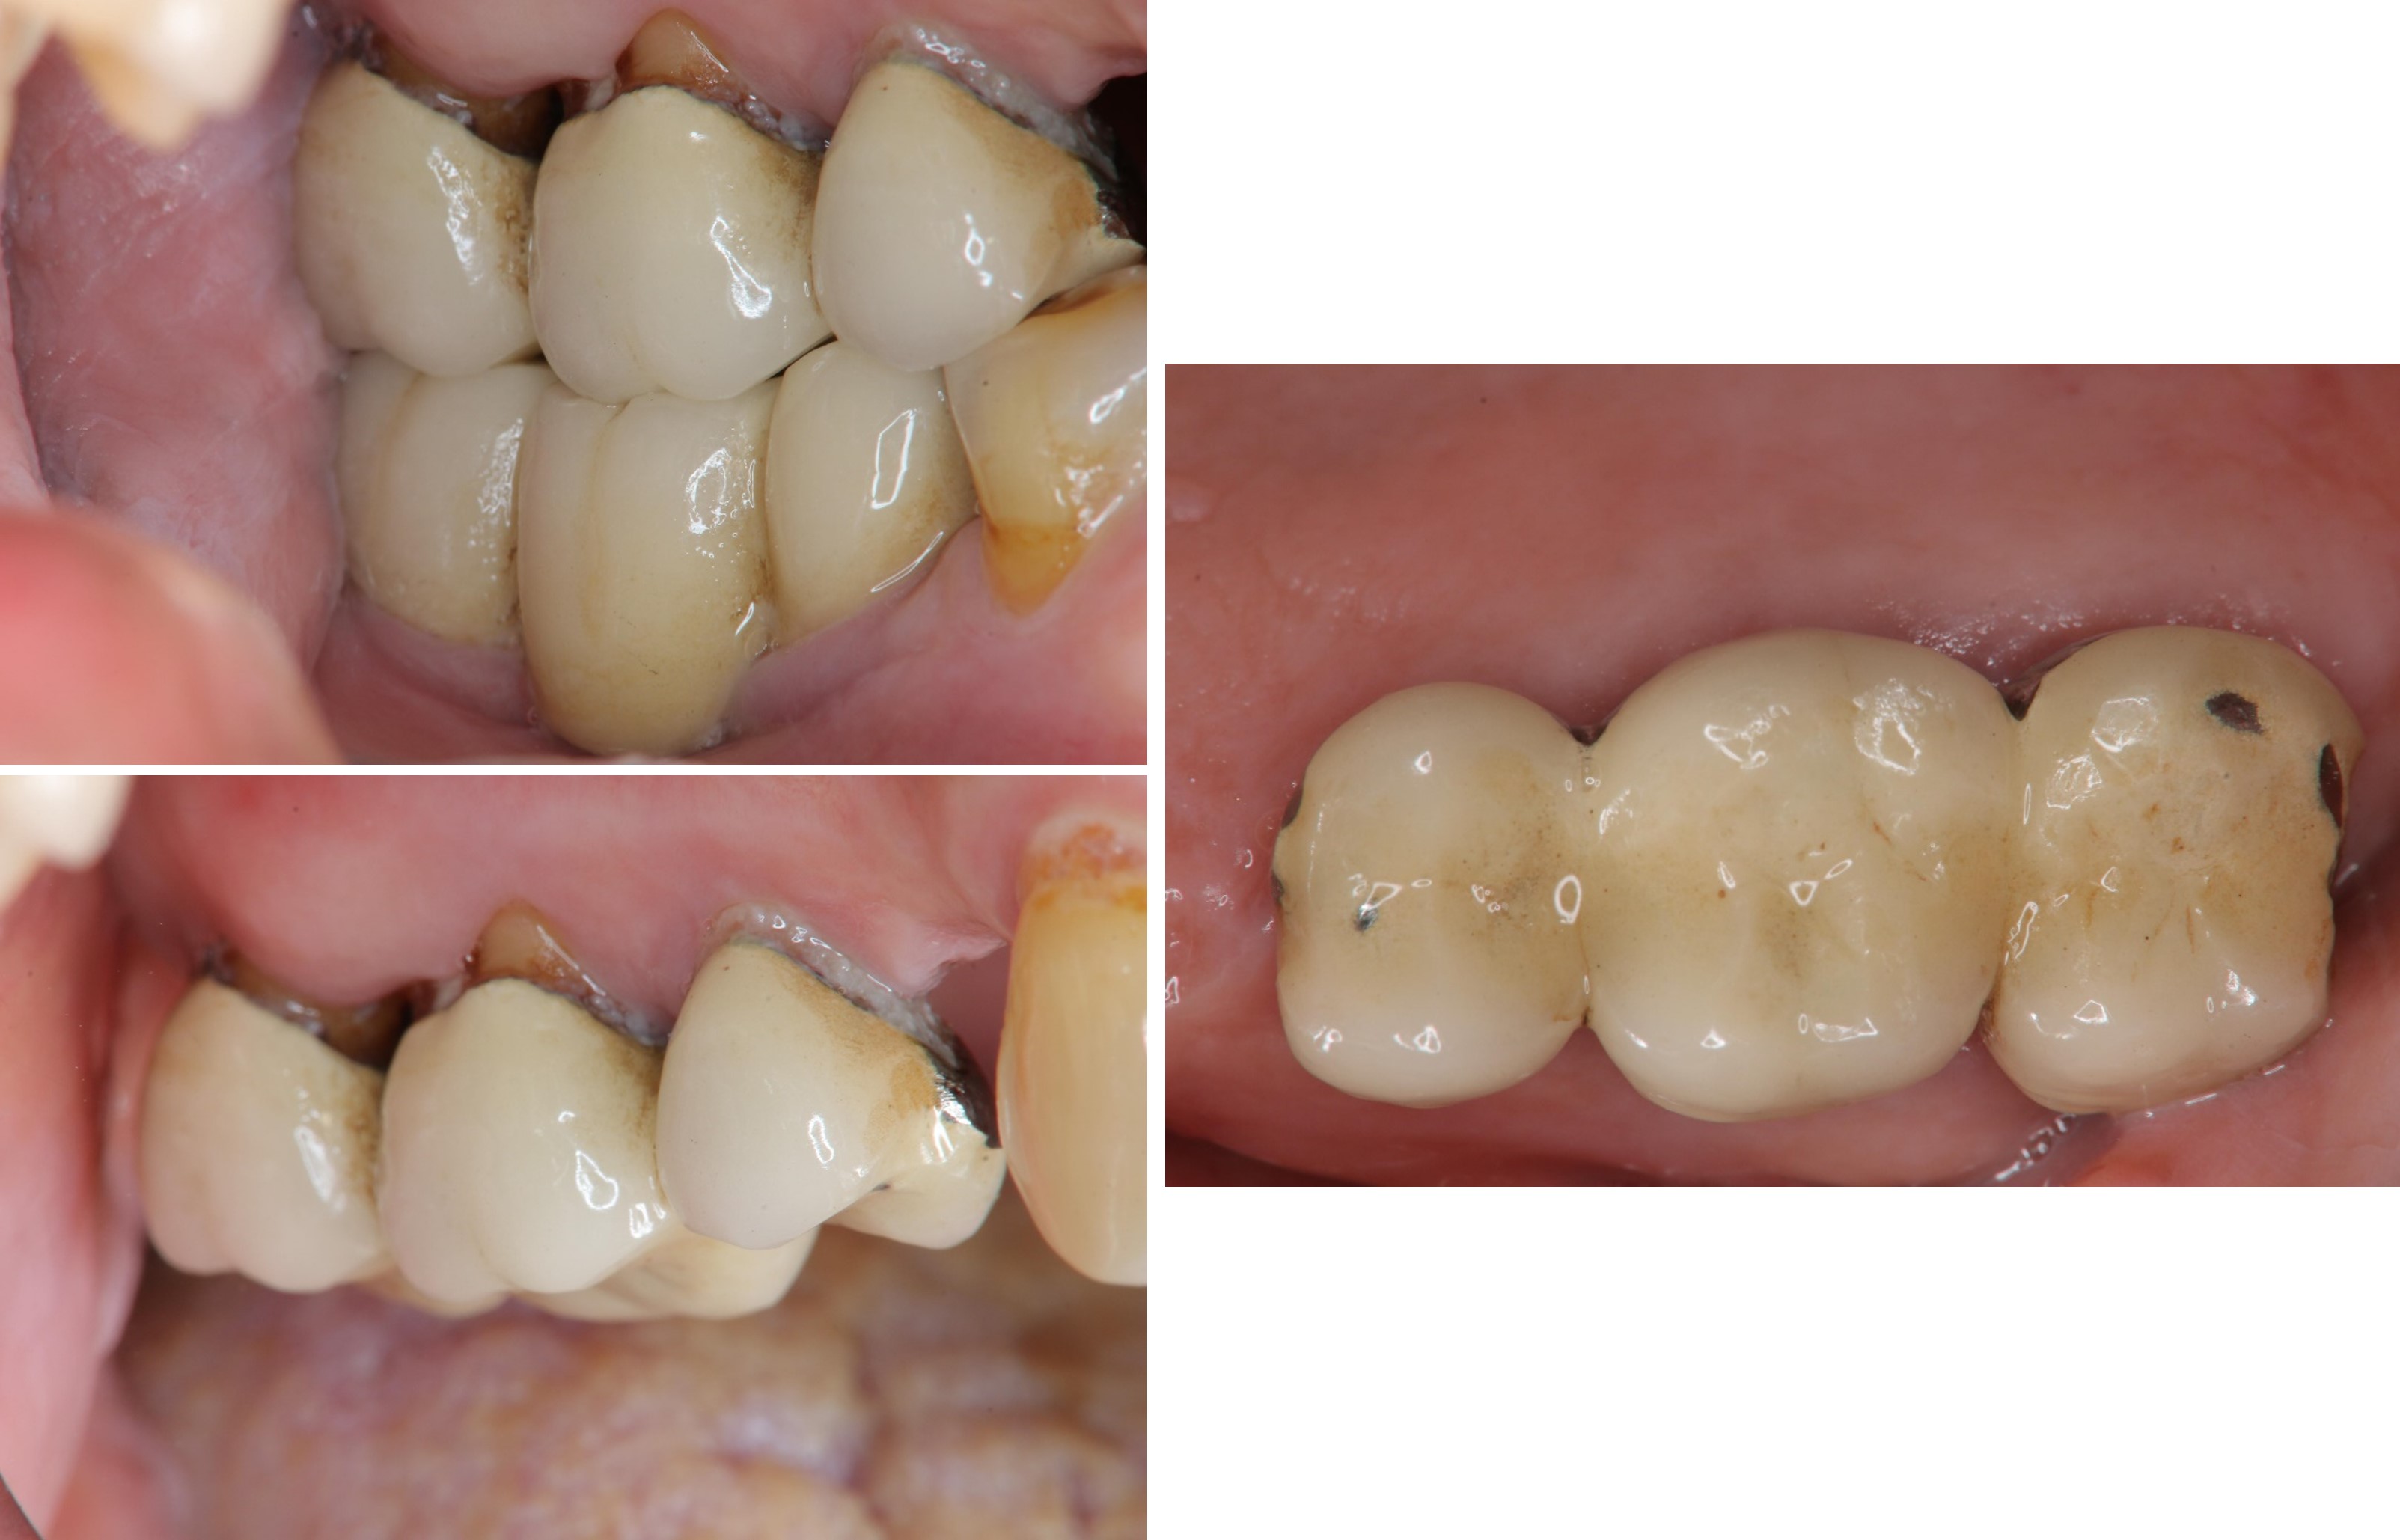

膺復前評估牙齦、牙齒狀態

治療後,咬合良好

治療後,密合度良好